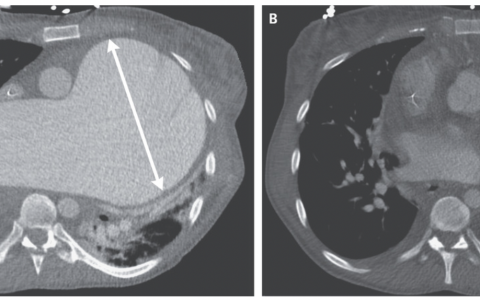

An 84-year-old man with benign prostatic hyperplasia who had been admitted to the hospital with acute kidney injury due to obstructive uropathy was noted to have gray skin. The skin changes had been present for 5 years. On physical examination, diffuse slate-gray pigmentation of the skin, particularly on the face, hands and nails, and sclera, was seen. A skin biopsy revealed small, dark granules in the basement membrane of sweat glands and in pilosebaceous units, blood vessels, and elastic fibers in the dermis. What is the diagnosis?

血清银水平为423纳摩尔每升(参考值,<10)。诊断为全身性银质沉着症。全身性银质沉着症是由系统性银暴露引起的,导致皮肤色素沉着不可逆地变暗。肤色变化在阳光暴露的区域最为明显,因为阳光催化了元素银的还原。患者在他几十年的服务员工作中没有显著的银暴露。他没有使用含银的产品,比如胶体银。他公寓楼里其他居民也没有肤色变化。出院时,患者被推荐进行进一步的毒理学评估。最终,银暴露的来源没有被识别。